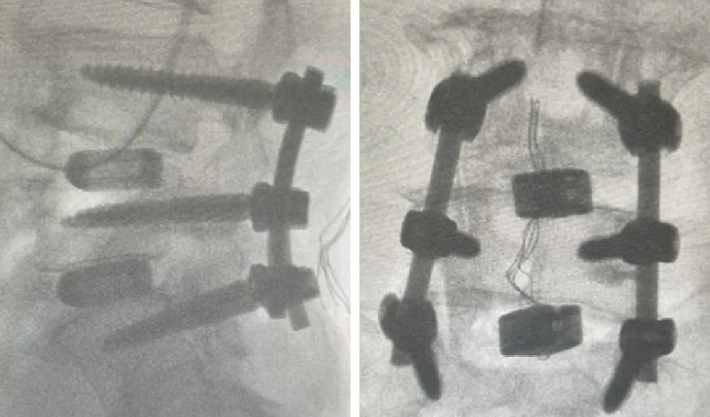

近日,beat365在线唯一官网第六附属医院(新疆维吾尔自治区骨科医院)脊柱外三科在医疗技术上取得新的突破,成功为两位腰椎手术患者利用3D打印融合器实施了腰椎椎体间融合术,患者术后恢复良好。

随着人口老龄化趋势不断加剧,腰椎间盘突出症、腰椎管狭窄症、腰椎滑脱等已成为常见的退行性脊柱疾病之一,严重影响中老年人的生活质量和身心健康。腰椎椎体间融合术是解决退行性脊柱疾病的常用手术方式之一。然而,在老年人骨质疏松、骨含量低的情况下,容易发生植骨融合失败的后遗症。3D打印融合器能有效解决这一问题。这两例手术中所使用的融合器,是通过3D打印技术制造的一种新型的多孔钛合金椎间融合器,它的微观和宏观结构模仿了人体椎体的天然骨小梁,更加贴合人体结构。同时,进一步优化了材料表面,使其具有更好的生物相容性和成骨活性,能够帮助新生骨快速长入融合器,加速愈合。该融合器还很适合微创手术,不需要再植入自体骨或其他骨修复材料,不仅提高了治疗效果,还减少了患者的手术创伤。